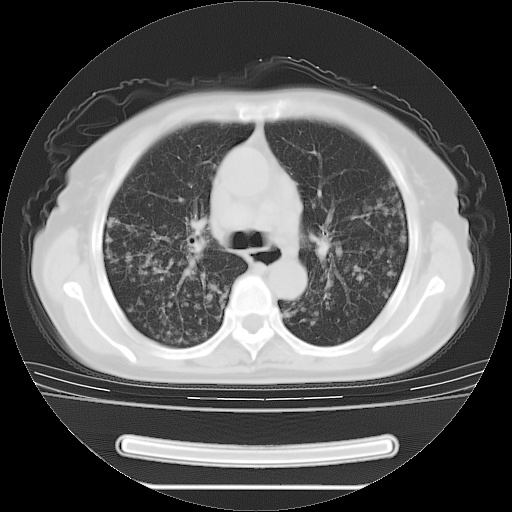

患者女性,72岁,慢性咳嗽3月余,曾抗炎治疗无效果,最近抗结核治疗约半月余,症状缓解。

ct示两肺粟粒状病灶,以两肺上叶尖后段及下叶背段分布为主;首先考虑结核。请战友们分析。

考虑 1 弥漫性泛细支气管炎, 2 结核不除外/.  有小叶中心结节 和 树芽征!!

两肺内病灶呈小结节状和树芽状,纵膈的肿大的淋巴结密度不均匀,并见有钙化,考虑为两肺结核可能更大些。

两肺内病灶呈小结节状和树芽状,纵膈的肿大的淋巴结密度不均匀,并见有钙化,多形态病灶,考虑为两肺结核,肝内考虑小囊肿。

片子很好,质量很高,两侧肺门淋巴结肿大并有钙化,两肺弥漫病灶,首先考虑tb并播散,但年龄大了呀(72岁)小细胞肺癌不能除外,如果是肺癌也没什么大的治疗了,建议正规抗结核治疗后复查

两肺内病灶呈小结节状和树芽状,纵膈的肿大的淋巴结密度不均匀,并见有钙化,结合(曾抗炎治疗无效果,最近抗结核治疗约半月余,症状缓解。)

考虑为两肺结核可能更大些。